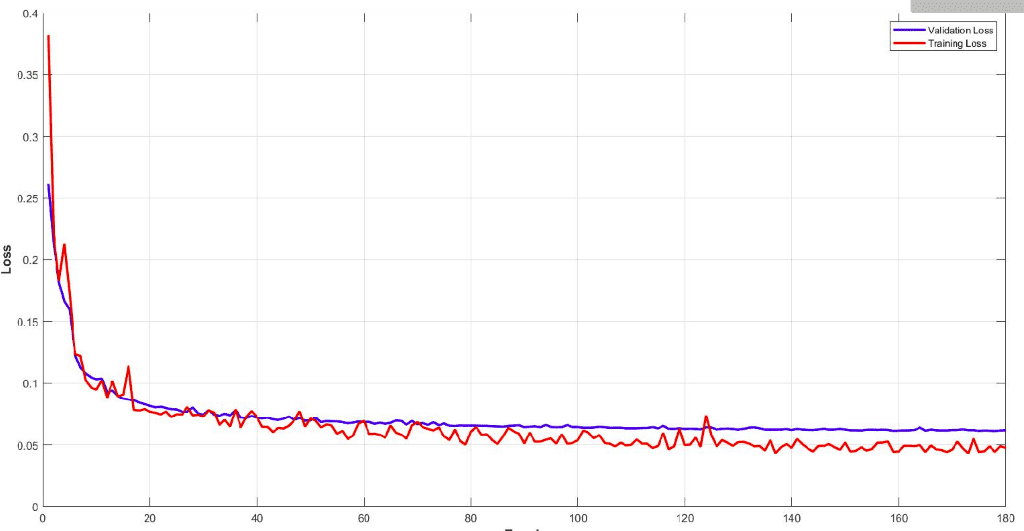

下面你可以看到模型的训练和验证骰子损失曲线。监控您的模型性能并调整参数以获得如此平滑的训练曲线非常重要。很容易理解这个模型的效率。

该模型在子卷的验证集中达到了大约 93% 的骰子系数分数。最后但同样重要的是,让我们看看验证集中 3D-Unet 的一些可视化预测。尽管预测是 3D 体积,但我们在这里只展示一个代表性切片。通过获取 MRI 的多个子体积,可以将它们组合起来形成完整的 3D MRI 分割。请注意,我们使用子卷采样的事实是数据增强。

最近我们还使用 Pytorch 添加了Tensorboard可视化。这个惊人的功能可以让你保持清醒,让你跟踪模型的训练过程。您可以在下面看到一个保留训练统计数据、骰子系数和损失以及每类分数以了解模型行为的示例。

很明显,不同的组织具有不同的精度,即使从训练开始也是如此。例如,查看验证集中从高值开始的空气体素,因为它是不平衡数据集的最主要类别。另一方面,灰质从最低值开始,因为它最难区分且训练实例较少。